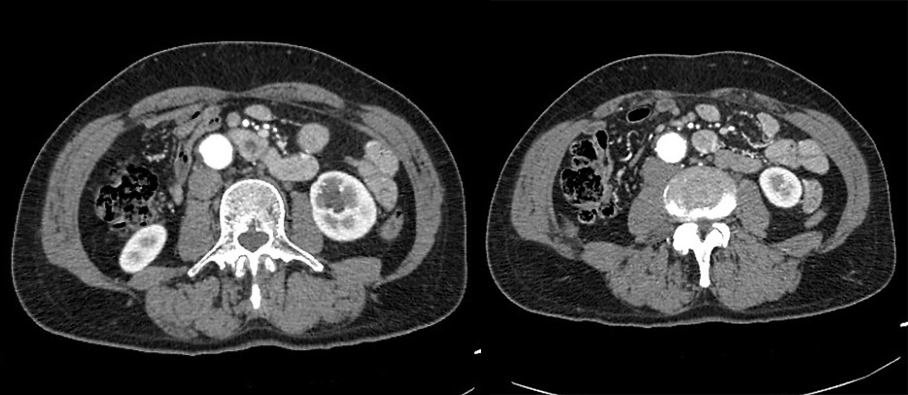

1、静脉尿路造影:表现为肾实质内圆形、边缘光滑的对比剂充盈区,有时可见与肾盏相通的细长管道。合并结石表现为囊腔内高密度影。

红色箭头所指为憩室,黄色箭头所指为肾盏。